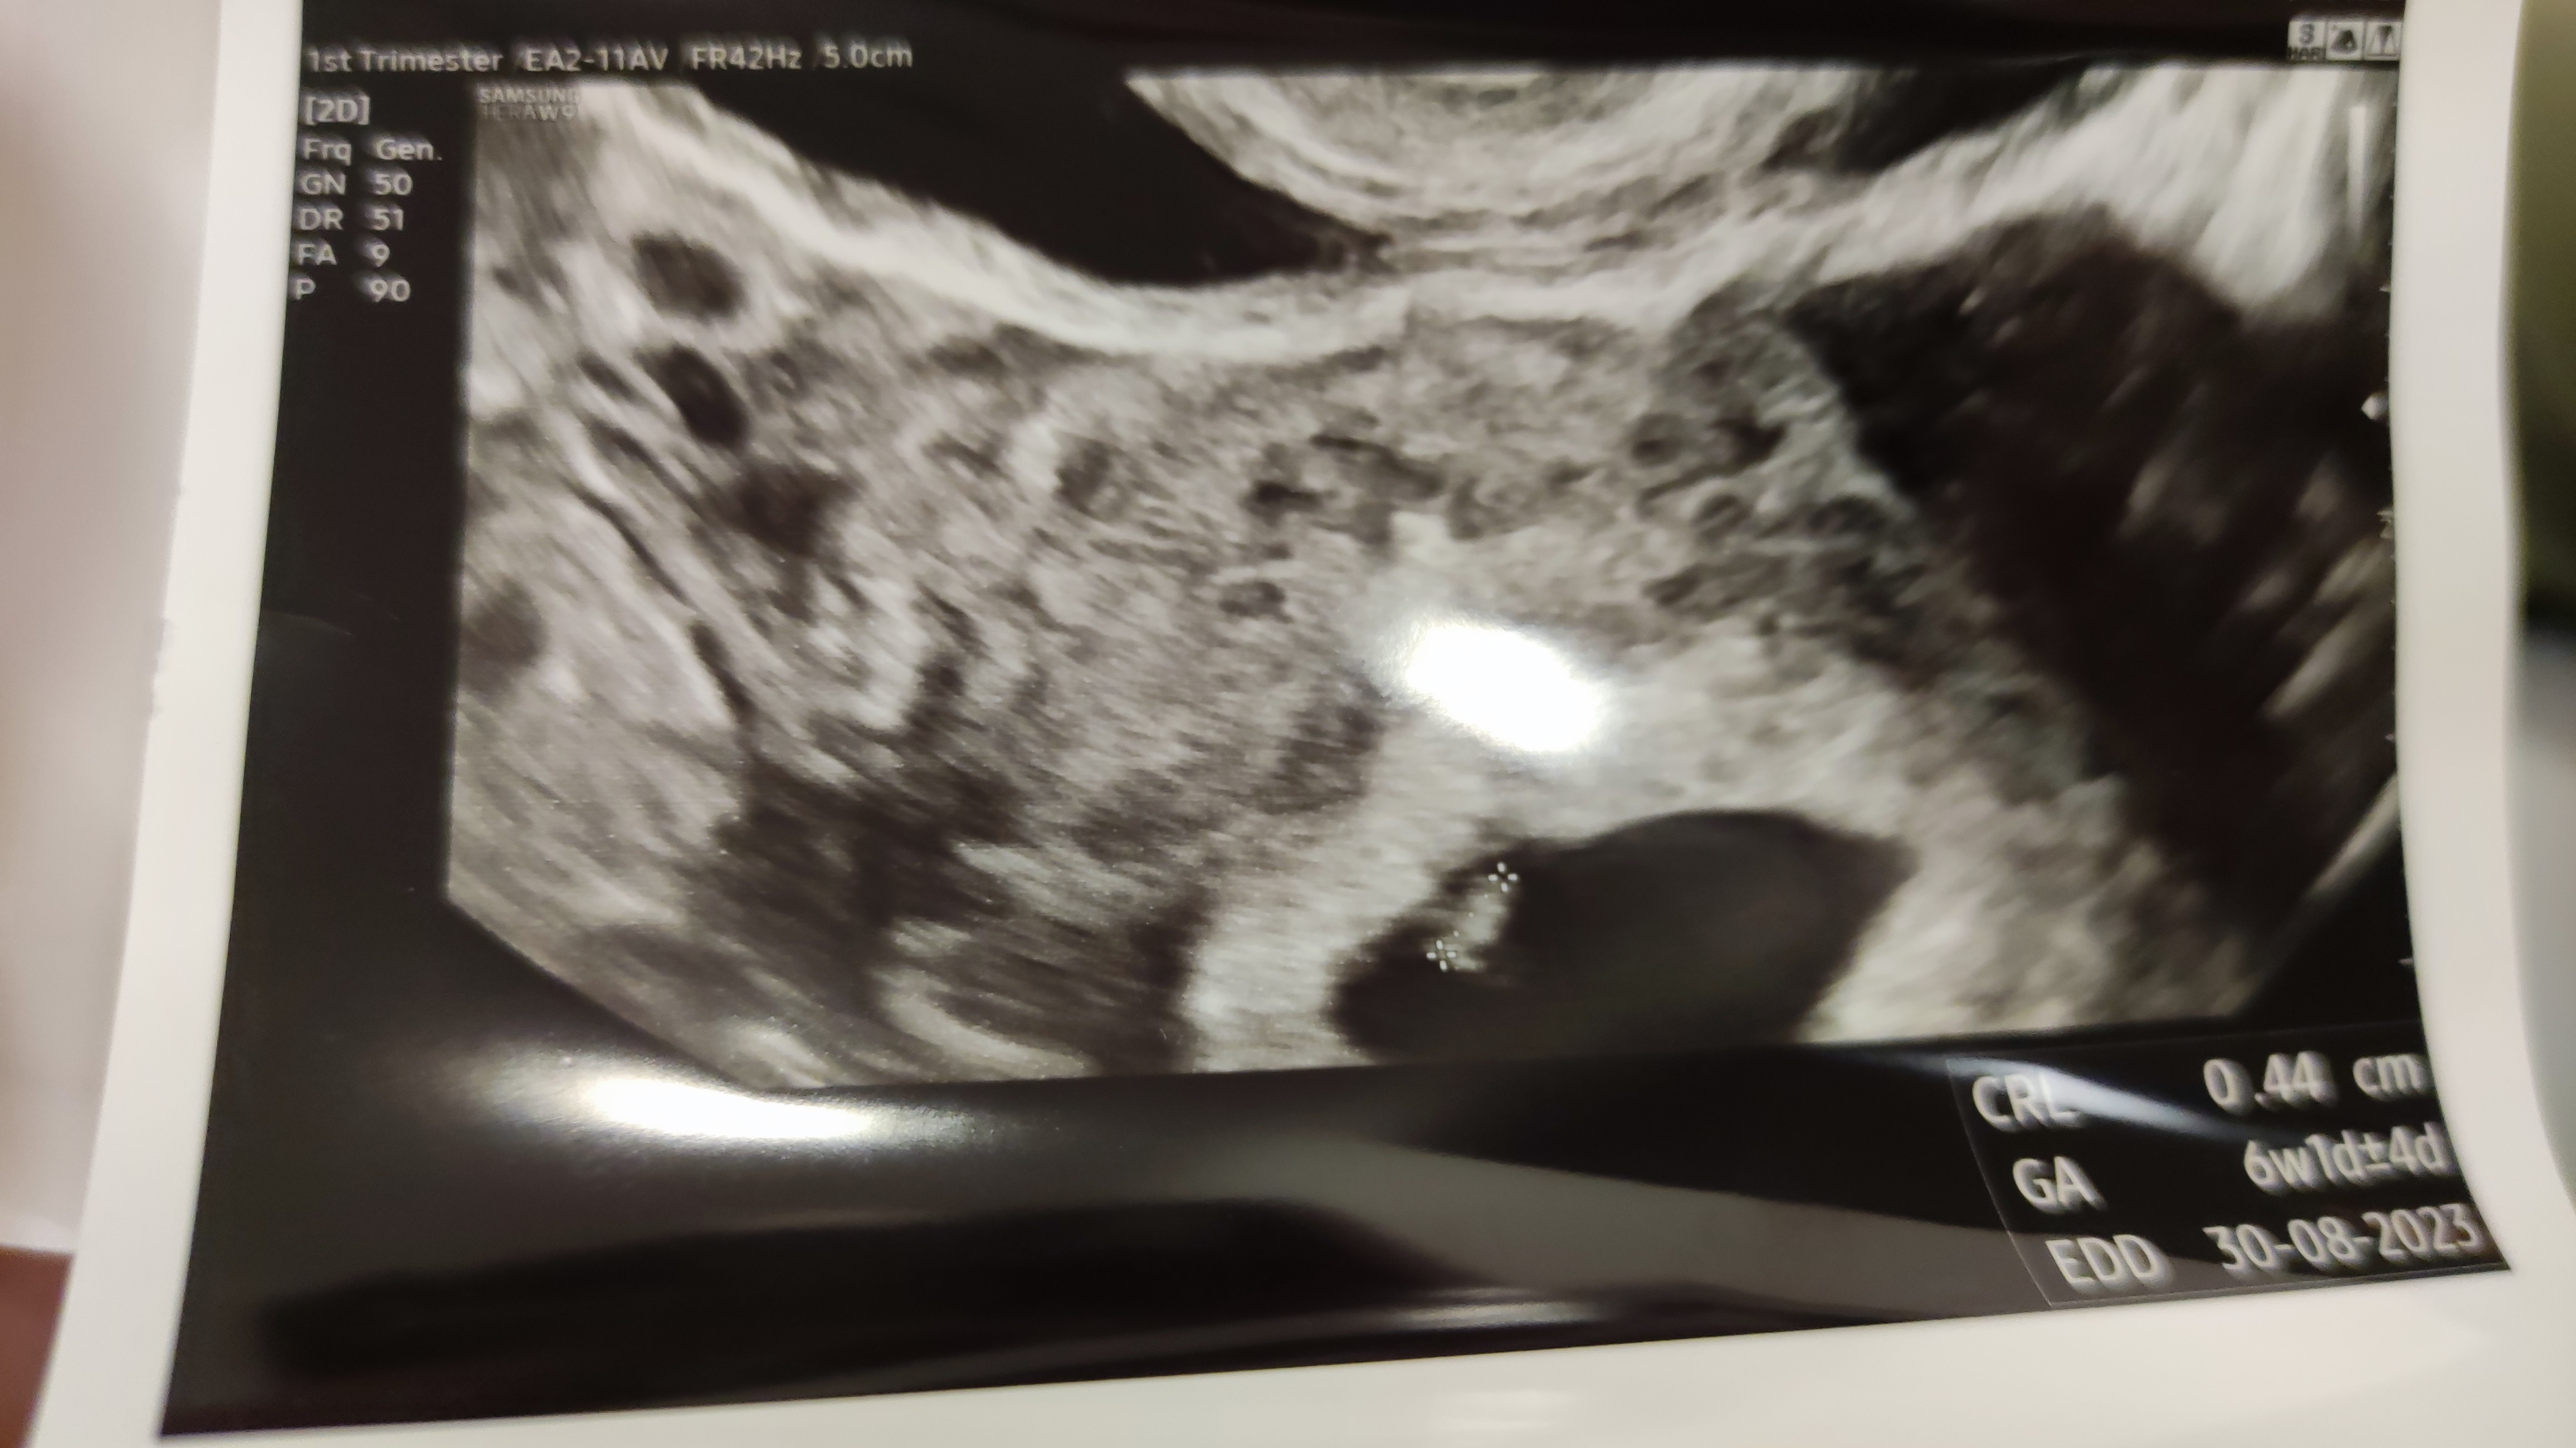

Zdjęcie robione kalkulatorem sorki 😂😂😂

44 mm dzidziucha. 6t1d, serducho powoli się rozkręca.

Krwiak obecny ale się obniżył więc znowu muszę leżeć :)